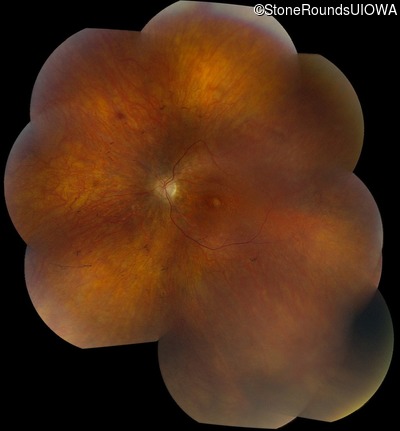

Fundus Montage - Right - 5/180

Exemplar